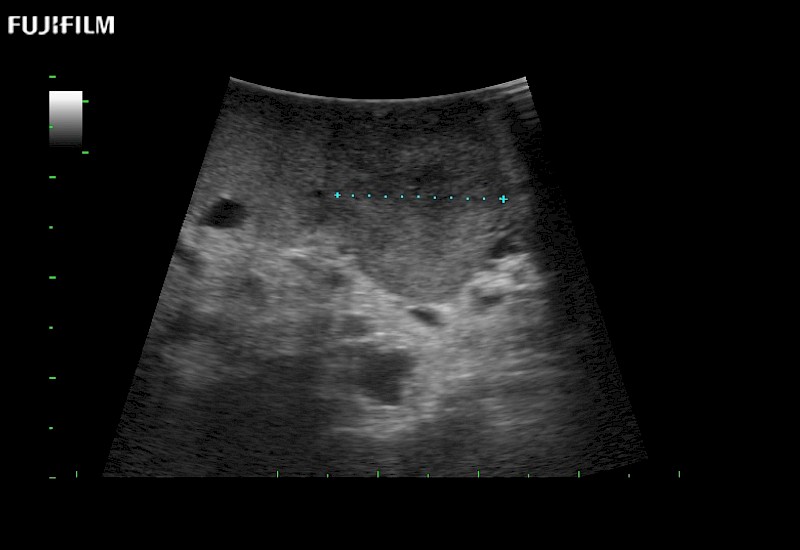

Our dedication to Laparoscopic Surgery allows us to offer superior image quality, outstanding system reliability and intuitive use of cutting edge technology.